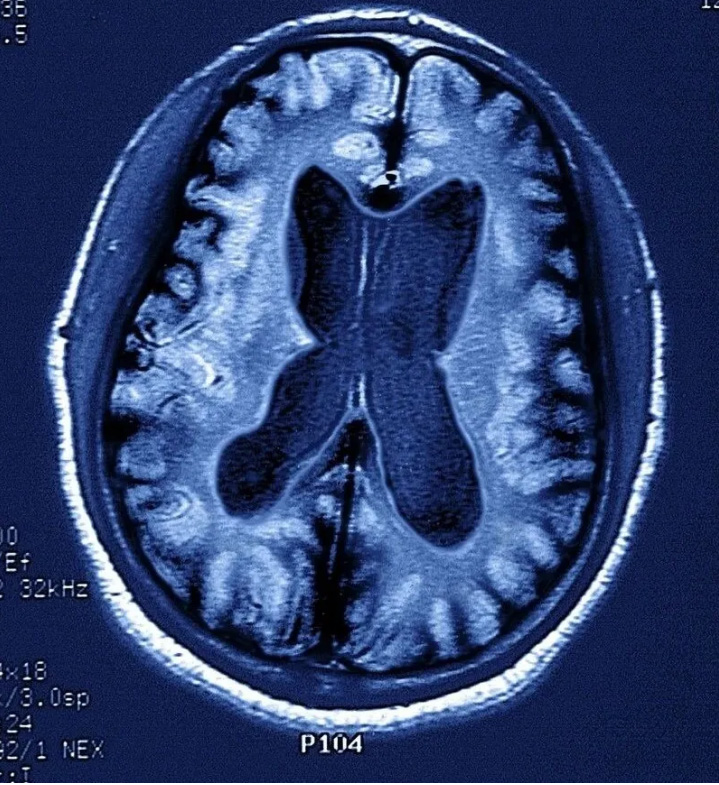

一般來說,記憶力下降是失智癥的核心癥狀,但它不是診斷失智癥的充分條件,目前臨床上診斷失智癥還要結(jié)合其它手段,如一系列的量表評估,MRI等客觀檢查。

因而當(dāng)記憶出現(xiàn)問題時(shí),可就診于各大醫(yī)院神經(jīng)內(nèi)科記憶門診,完成一系列的神經(jīng)心理學(xué)量表測試、抽血檢查(查APOE ε基因型等)、腰穿腦脊液檢查(Aβ1-42的檢測)、尿和便標(biāo)本、普通頭顱核磁,如有必要還需做PET-MRI以檢測腦內(nèi)淀粉樣蛋白沉積。通過上述的綜合測試評估病情,給予診療意見。